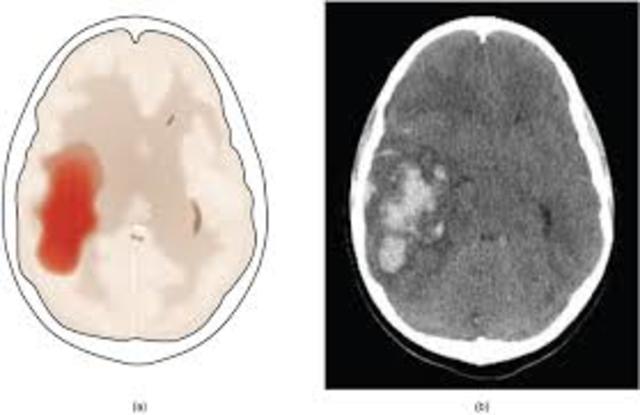

Isquemia Global 1

Las fuentes de energía (glucosa y glucógeno) se agotan en el transcurso de 2 a 4 minutos; y los depósitos de celulares de ATP, en 4 a 5 minutos.

El ingreso de sodio excesivo a la célula conduce a edema celular e intersticial.

La falta de flujo de calcio desencadena una cascada de mecanismos que provocan la destrucción de la célula.

El patrón de la isquemia global refleja la disposición anatómica de los vasos sanguíneos cerebrales y la sensibilidad de los distintos tejidos cerebrales a la falta de oxigeno.